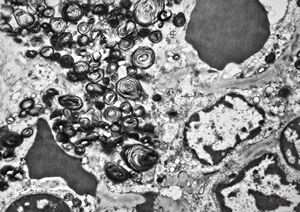

M, 6m. | Niemann-Pick disease - spleen